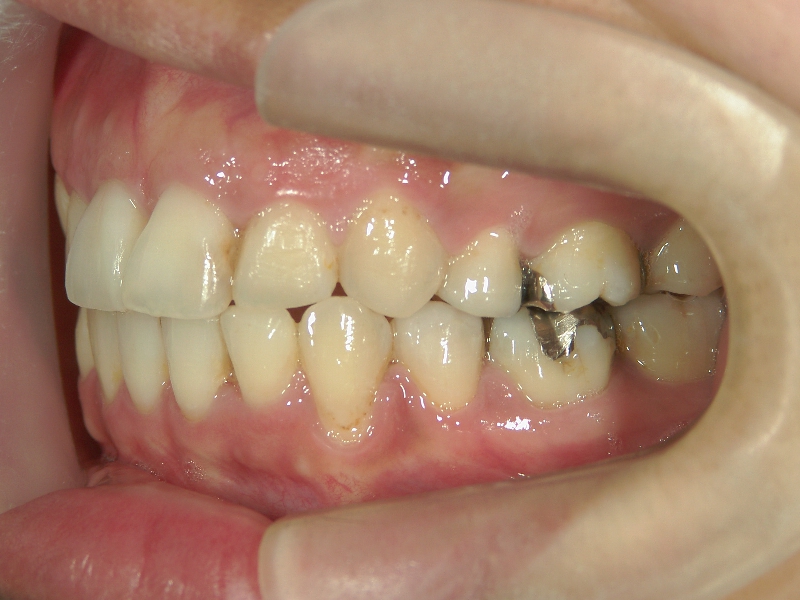

矯正歯科 治療前矯正歯科 治療前

矯正歯科 治療前 上下左右4番 計4本を抜歯して叢生を改善しました。

no.31_1962_治療前_右.JPGno.31_1962_治療前_正面.JPGno.31_1962_治療前_左.JPG